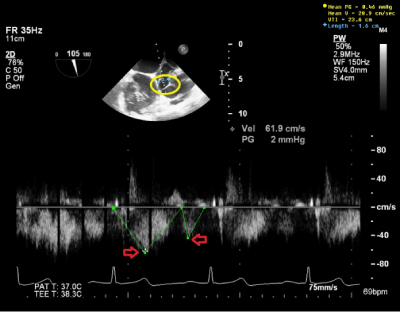

Intraoperative TEE ME SAX AV view with color Doppler shows a mosaic color pattern indicating blood flow in enlarged left main coronary artery and the fistula tract behind (Figure 3A). TEE ME Bicaval view with color Doppler indicates blood flow in distal left main coronary artery fistula and giant fistula aneurysm (Figure 3B) with different channeling tunnels seen per 3D (Figure 3C & Figure 3D), forming a complex network of trafficking communication between distal fistula tract, right atrium and giant aneurysmal CAF dilatation. The pulse wave Doppler through distal fistula tract allowed us to calculate velocity time integral (VTI) of 23.6cm (Figure 4). By equation: Volume=Area X VTI, the volume per heart beat shunted via fistula is calculated to be 47.2ml, using the measured cross sectional fistula diameter of 1.6cm (Area=2cm2), which equated to be 3.26L/min for the flow rate across the fistulous tract considering patient’s heart rate of 69beats/min. This shunting volume and flow rate indicated a significant L-R shunt, which correlated well with patient’s high CHF symptoms.

Our described case of a giant aneurysmal fistula draining into the right atrium was congenital and had grown with time. In this case, it caused a high cardiac output state with likelihood of coronary steal phenomenon. From the appearance on CT scan, we doubt a percutaneous approach would have been successful. The giant aneurysm fistula was seen to dilate to its maximum size at the end of systolic phase of cardiac cycle and soon after atrial kick during diastolic phase per echocardiography and pulse wave Doppler (Figure 4). The dynamic change of the aneurysmal size is due to continuing change of pressure gradients between fistula tract and right atrium, between fistula tract and aneurysm, and during different phases of cardiac contraction and relaxation. Under LaPlace’s Law, which describes the relationship between the transmural pressure (P) and the tension (T), radius (R), and thickness (T) of the vessel wall (P=k x 2HT/R) where k is a constant number, this condition could dramatically increase the aneurysmal fistula’s tension as such even a slight impact from a coiling procedure might make it prone to rupture. If the fistula were to have a narrow origin and ending, percutaneous treatment with a coil or a vascular plug in both ends could have been attempted.

Figure 4 TEE ME Bicaval View with pulse wave Dopper of distal CAF. Red arrows show total velocity time integral (23.6 cm) of flow per heart beat through the fistula tract. The volume through CAF is calculated to be 47.2 ml with measured fistula diameter of 1.6 cm.